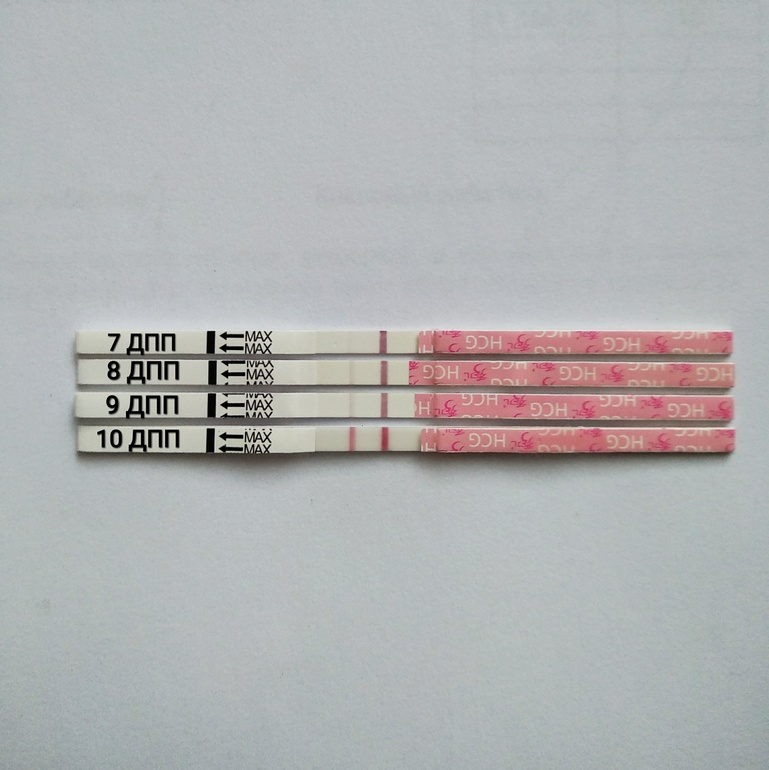

Ниже динамика тестов с 7 по 10 дпп.

Полосочки быстро ярчали, и я заподозрила двойню) Естественно, чему удивляться если подсаживали двоих?